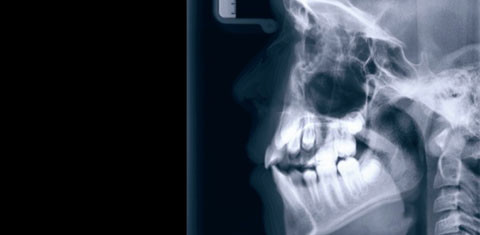

WIEN – „Das Kiefergelenk ist das wichtigste Gelenk im Körper“, schrieb Dr. George Goodheart, Begründer der Applied Kinesiology. Kaum ein kompetenter Therapeut im Bereich des Bewegungsapparates wird heute bestreiten, dass das Kiefergelenk mit seiner Arbeits- und Stützmuskulatur wichtig ist, aber dass es das wichtigste Gelenk sein soll, dürfte möglicherweise überraschen.

Seit über 40 Jahren beschäftigt sich Prof. Harold Gelb, Leiter der Pain Clinic an der Tufts University in Boston, mit dem Problem Kiefergelenk und Statik. Seine These: „Gehe von orthopädischen Idealverhältnissen und -proportionen aus und versuche, diese auch und gerade für Gesicht, Schädel, Mandibula und Kiefergelenk (wieder) herzustellen.“ Er setzte als einer der ersten die Tatsache um, dass die Stellung der Zähne und die vertikale Dimension entscheiden, wie der Condylus mandibularis in der Fossa articularis des Os temporale zu liegen kommt und dass nicht die Muskulatur und nicht das Gelenk, sondern die Stellung der Zähne – und somit die Interkuspidation (IKP) – entscheidet. Mit Kunststoffschienen auf den Unterkiefer versuchte Prof. Gelb die Körperhaltung zu beeinflussen. Der Forscher vertritt die Meinung, dass das Kiefergelenk dem Stütz- und Bewegungssystem übergeordnet ist und Störungen desselben wiederum das Kiefergelenk (Ursache und Folgekette) beeinflussen.